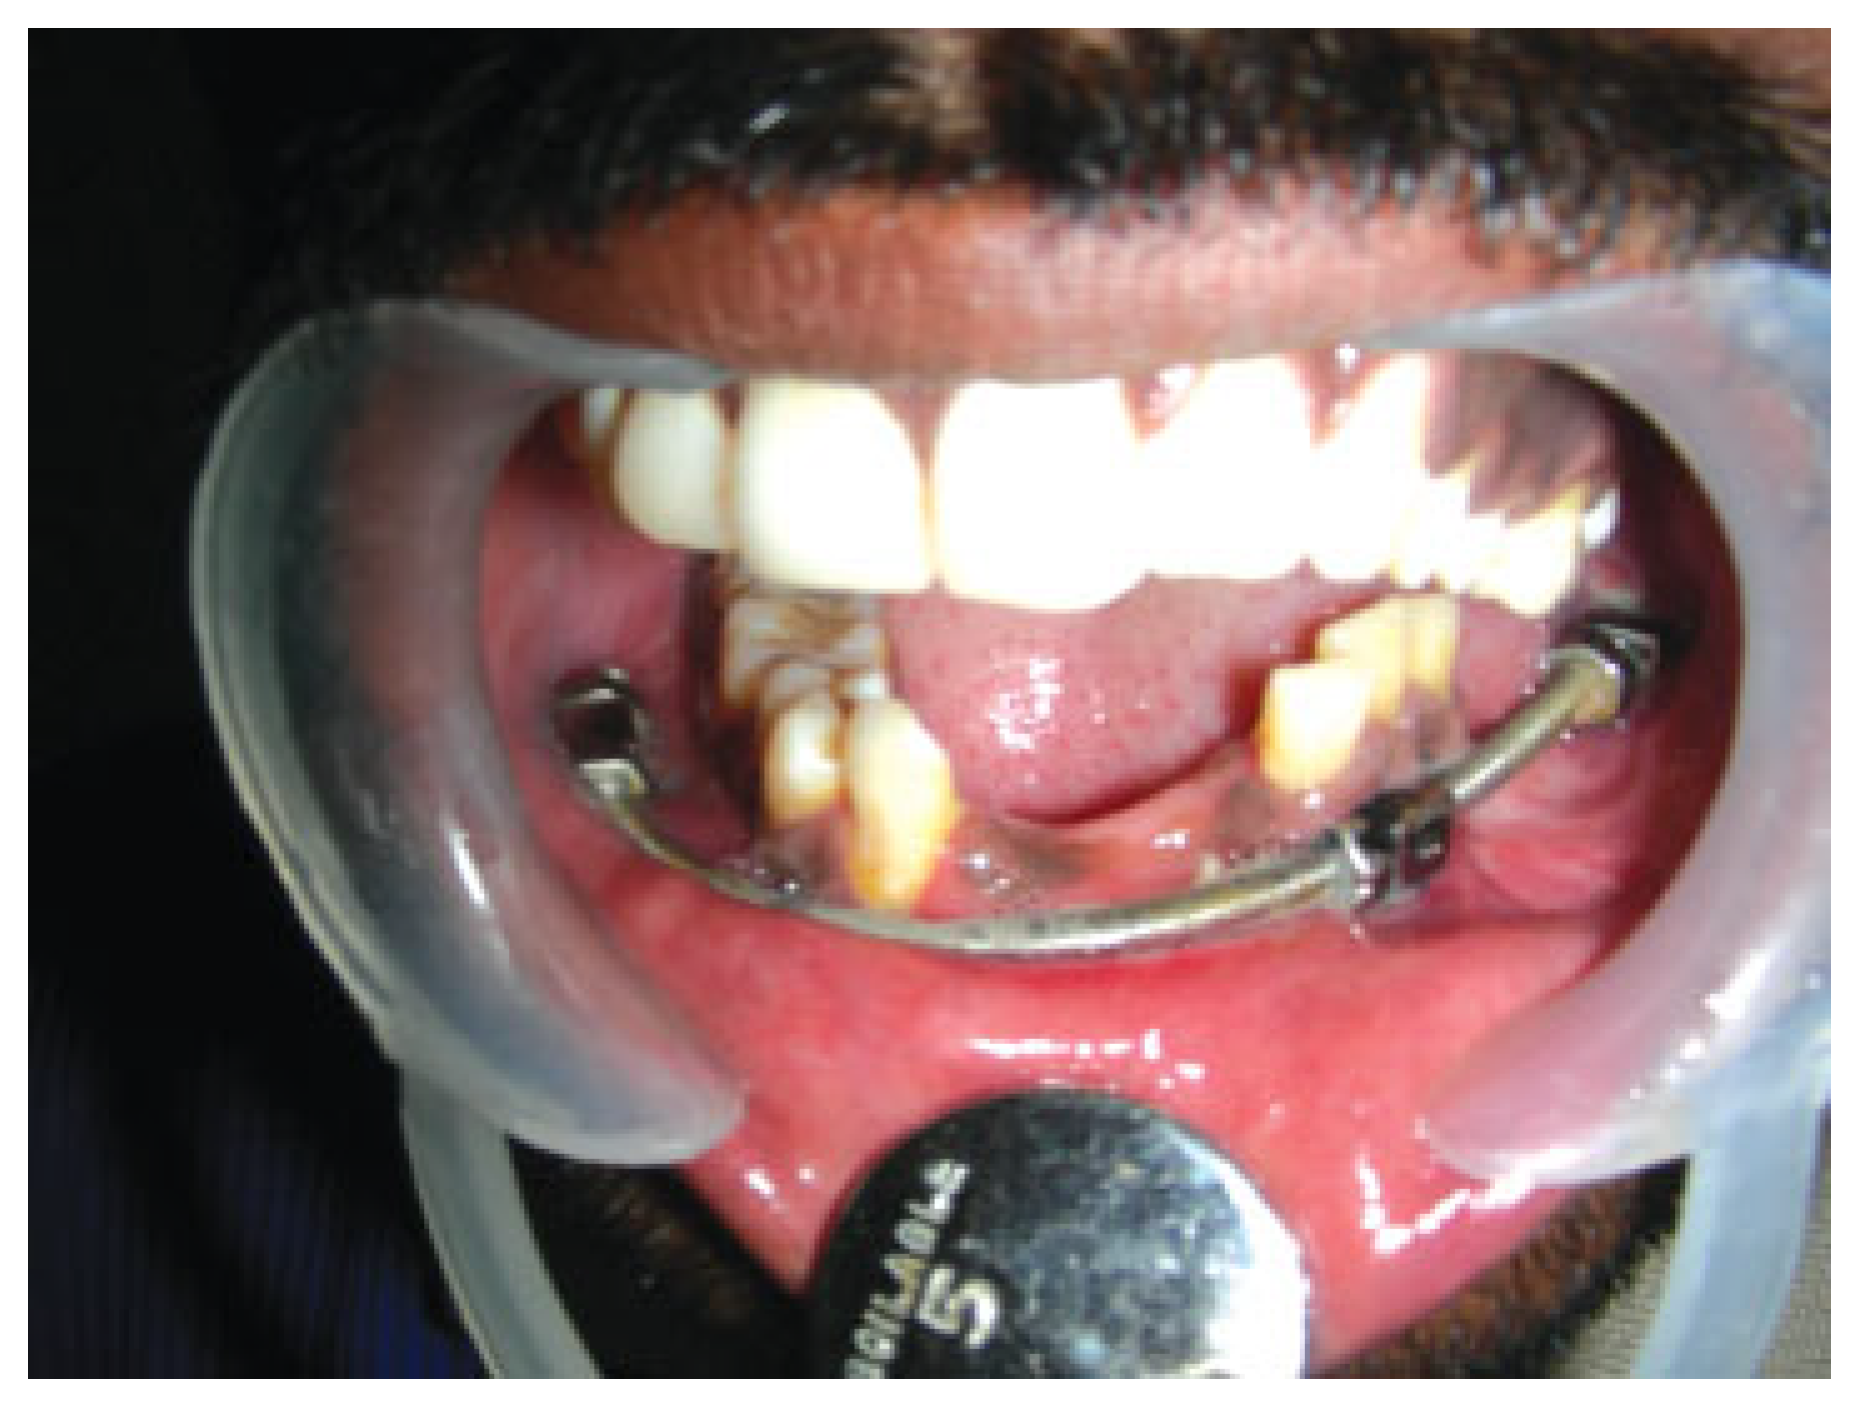

Case 2. Following consolidation. Frontal view.

Figure 14.

Case 2. Intraoral view with the device following consolidation. Note the teeth included in the transport segment at the left posterior mandibular region.

The existing reconstruction plate was removed and the device was assembled and fixed in situ through a combined oral and extraoral approach (Figure 11). After a latency period of 7 days, activation was performed for a period of 28 days until the transport disc reached the mandibular body region. A consolidation period of 2 months was felt to be mandatory and only the oral component of the appliance was removed (Figure 12, Figure 13, Figure 14 and Figure 15).